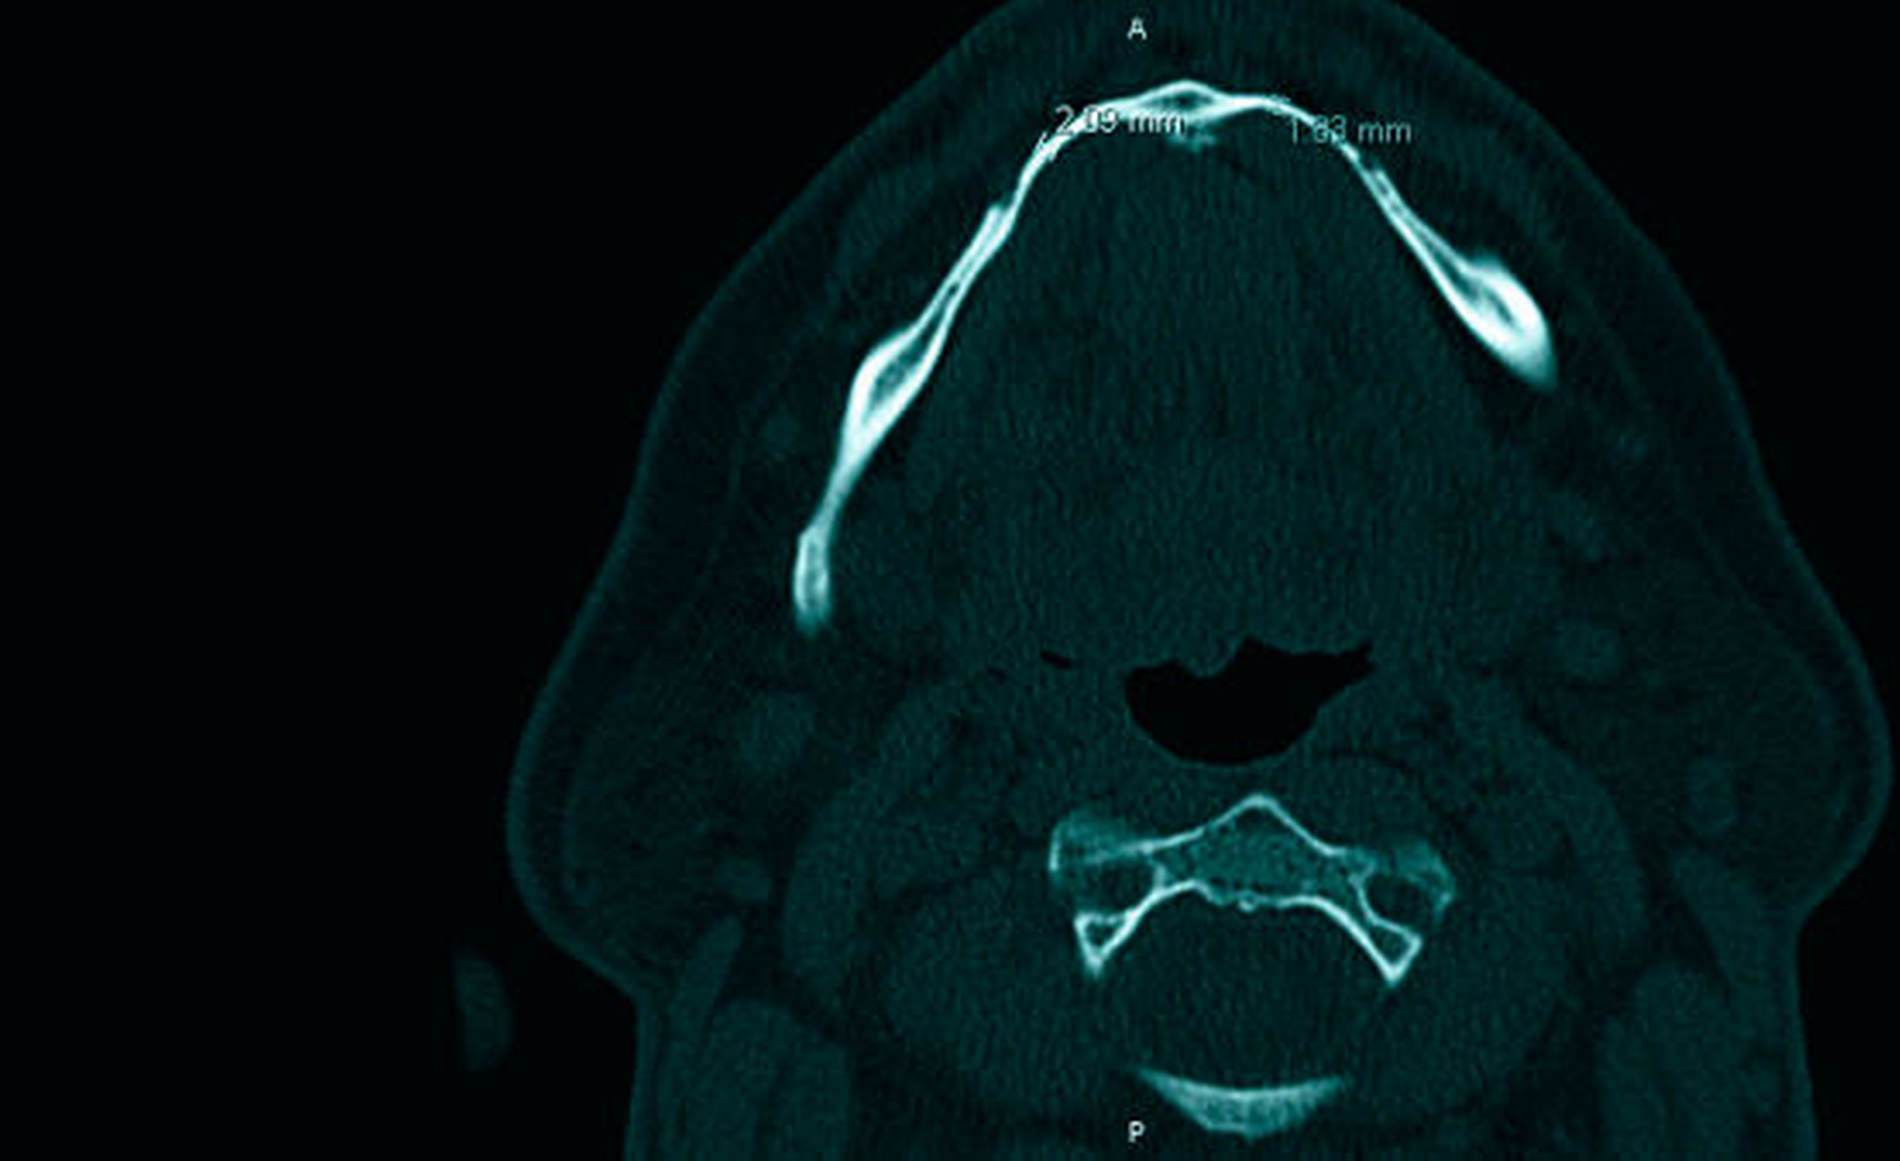

Dort stellte sich der Alveolarfortsatz im Unterkiefer regio 35 bis 45 sanduhrförmig dar (Abbildungen 4 bis 6), stellenweise nur zwei Millimeter stark und mit offensichtlich lediglich kortikalen Strukturen. Im Bereich der Muskelansätze verbreiterte sich die Mandibula entsprechend der anliegenden Belastung, korrespondierend dazu an den Alveolarfächern ebenfalls.